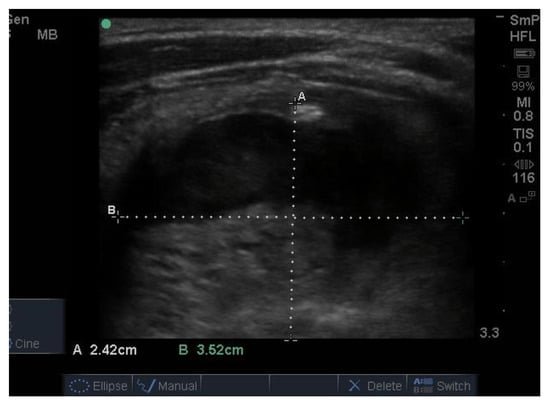

Three examples of papillary thyroid cancer are shown here. Firstly, a large typical papillary cancer with the characteristic microcalcifications is seen in Figure 11.

Figure 11.

Thyroid ultrasound from a patient with confirmed papillary thyroid cancer. The nodule is large (3 cm) and hypoechoic with an indistinct irregular edge and central microcalcifications. The calcifications are softer (less white) than seen above in some benign nodules and larger, around 2–3 mm (arrow). There is no halo. Not seen here, the blood supply was increased in the lesion and there was a feeding vessel on one side of the lesion. Another example of macrocalcifications in papillary thyroid cancer.

Secondly, a smaller but more hypoechoic lesion with obvious and larger soft microcalcifications and an irregular edge is shown in Figure 12. These two nodules are typical for papillary cancer and are reported from FNAB as “suspicious for papillary thyroid cancer”. In both cases this was confirmed at thyroidectomy

Figure 12.

Papillary cancer lesion with large fluffy microcalcifications, an irregular edge and overall hypoechoic texture.